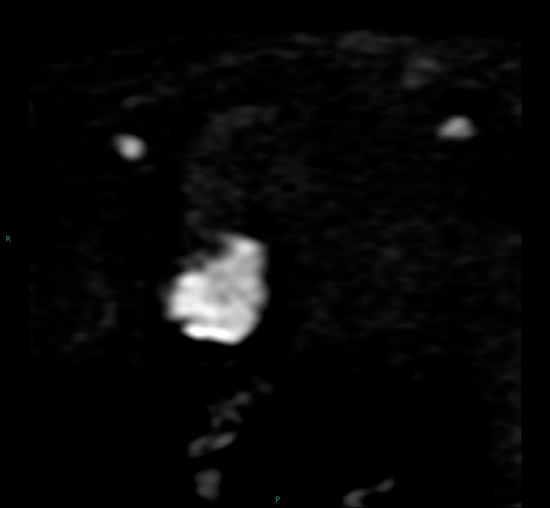

Figure 3a. DWI image in the same patient as Figure 2 shows the tumour to be high signal.

Diffusion weighted imaging relies on proton diffusion properties in water. Diffusion images are obtained using multiple B-values, and the tumour will be high signal on the high B-value image and then show low signal on the corresponding apparent diffusion coefficient (ADC) map (Figure 3a and 3b). The ADC map reflects movement of water molecules and represents capillary perfusion and diffusion. Images are assessed in conjunction with the T2 images at the same level.